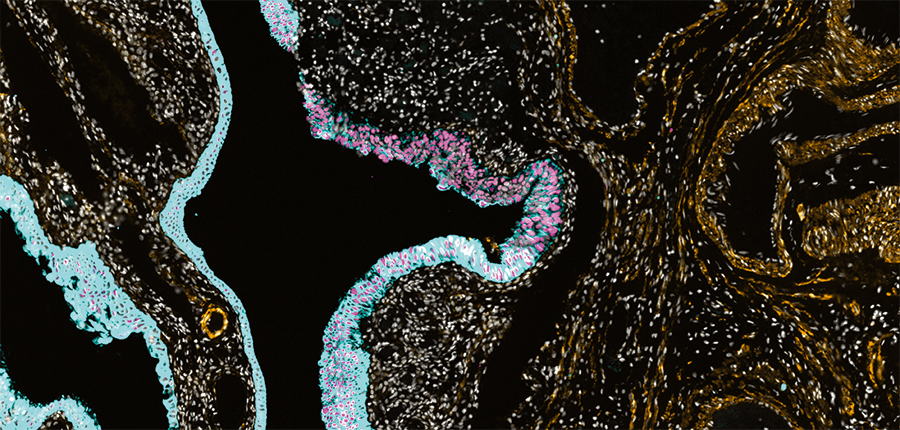

This microscopic view shows the molecular features of an early ovarian precancer (highlighted in aqua and pink). IMAGE: SANTAGATA LAB